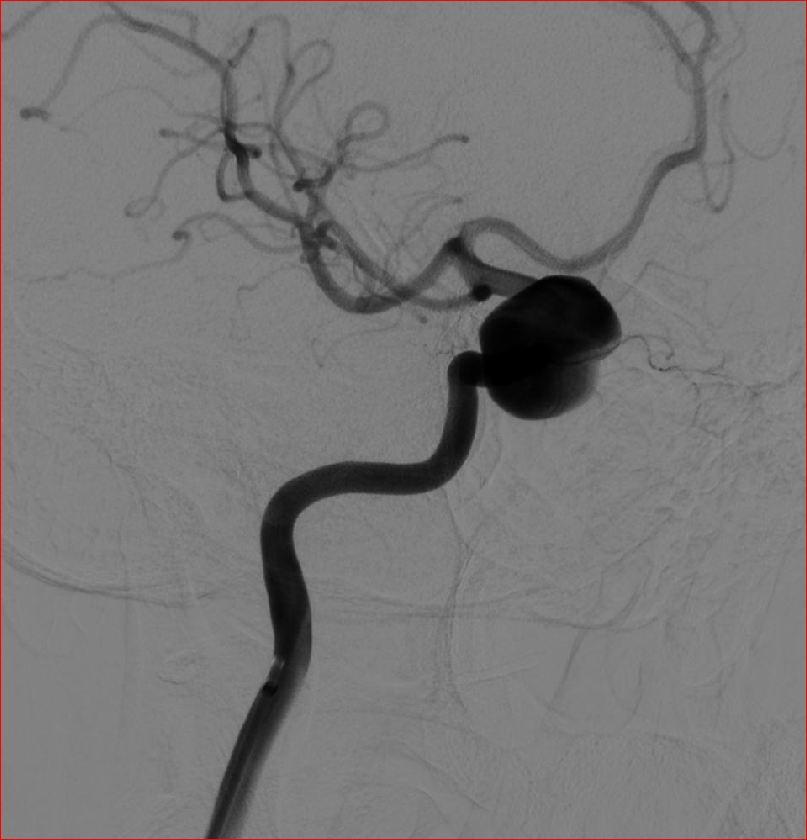

通过DSA(数字减影血管造影)明确脑内动脉瘤的诊断

目前颅内动脉瘤治疗的趋势是介入栓塞治疗,简单来说就是利用弹簧圈或其它器械,将动脉瘤腔填塞,使瘤腔内形成血栓从而起到治疗目的,对于一些介入治疗困难的动脉瘤可以采用开颅手术的方式夹闭,孤立、包裹、甚至采用搭桥手术治疗。